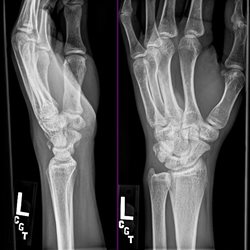

Various adult extremity cases. Shoulder, wrist, ankle, elbow.